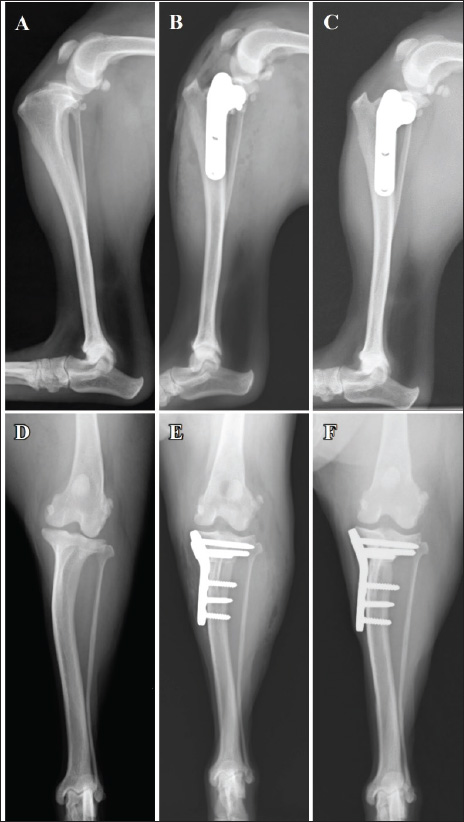

Radiography of the right stifle joint indicated infrapatellar fat pad signs and cranial tibial luxation (Fig. 1A). No obvious angular limb deformities were observed (Fig. 1A and D). Ultrasonography of the stifle joints (ARIETTA Prologue; Fujifilm Co., Japan; 18 MHz linear probe) revealed a complete CCLR, severe joint effusion, and medial buttress in the right stifle joint with no injury to the medial meniscus (Fig. 2A–C). Furthermore, partial CCLR and mild joint effusion were observed in the left stifle joint.

Fig. 1. Mediolateral radiographs (A–C) and caudocranial radiographs (D–F) of the right limb. The infrapatellar fat pad sign and cranial tibial luxation at the first visit (A). Absence of angular limb deformities (D). Placement of a 2.4-mm TPLO plate (B and E). No osteotomy line at the 14-week follow-up (C). No evidence of dislocation at the 14-week post-TPLO (F) follow-up.

Postoperative radiography revealed that the TPA was 5° on both sides. The owner was satisfied with the postoperative weight-bearing ability of the limb while walking at the 4-week follow-up visit. A faint osteotomy line was visible, and radiography revealed aligned and positioned TPLO plates and bone segments with no displacement. No tibial translocation was detected during the compression test. The dog was able to use its right hind limb without any discomfort at the 8-week follow-up visit. The osteotomy line had disappeared, and radiography revealed aligned TPLO implants. Tibial translocation was not detected during the compression test. Minimal discomfort upon waking up was reported at the 14-week follow-up visit for the right limb (4-week follow-up for the left limb); lameness was not observed while walking or trotting. The tibial compression test results were negative for both limbs, and the rotated bone fragment showed complete fusion with the tibia of the right limb (Fig. 1C and F). A faint osteotomy line was observed in the tibia of the left limb. Radiography revealed no dislocation of the bone or the TPLO implants on the right or left sides. The owner was pleased with the significant improvement in walking ability. By the 13-week follow-up visit osteotomy line in the left limb was not visible, with no residual discomfort or lameness in either limb. The osteotomy line was not apparent owing to bone union (Fig. 4C). The implant alignment and bones remained stable (Fig. 4F).